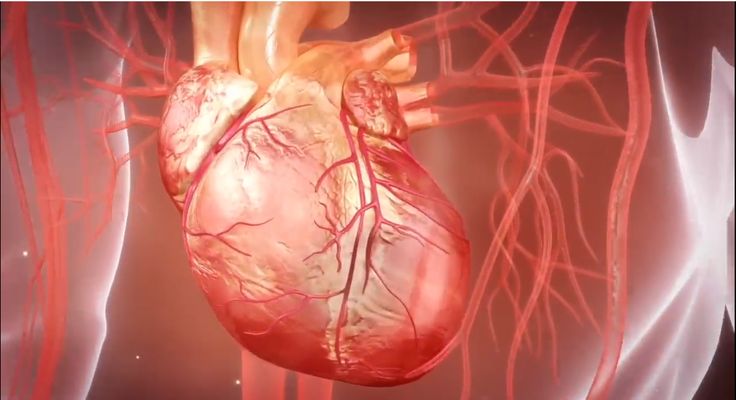

精准还原与深度解析: 它能够突破肉眼或显微镜的限制,精准构建并动态展示人体器官、组织、细胞甚至分子层面的结构与功能,揭示疾病发生机制、药物作用靶点或医疗器械的工作原理,为科研和教学提供无与伦比的洞察力。

模型构建: 专业三维建模师依据权威医学图谱、影像数据(CT/MRI切片)、器械CAD图纸或实物照片,构建高度精确的解剖结构、医疗器械、细胞分子模型。这是医疗技术三维动画真实感的基础。

材质与质感: 为模型赋予逼真的材质(如皮肤、骨骼、金属、塑料)和纹理,模拟生物组织的光泽、透明度、血液流动感等物理属性。

物理仿真: 运用动力学模拟技术(如流体、柔体、刚体动力学),逼真再现血液流动、组织变形、器械运动等自然物理现象。